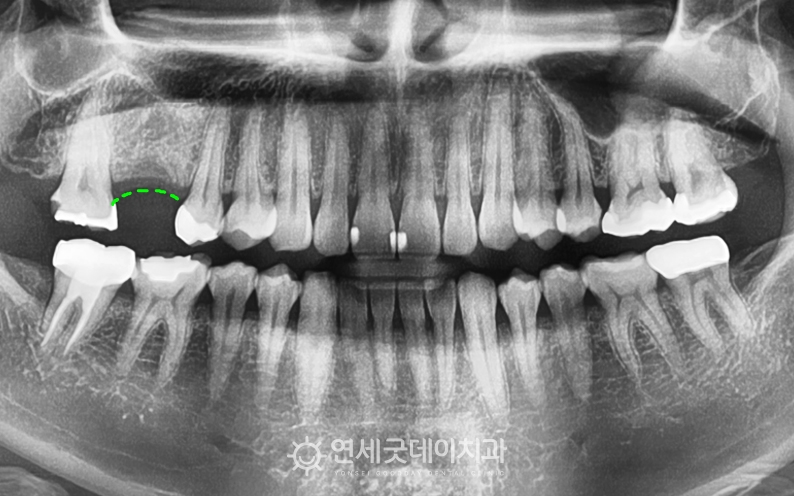

● 담당과 : 치주과 ● 치료요약 : 치아가 빠진지 오래된 부위(#16)에 잇몸뼈이식 및 어금니 임플란트 진행

치아가 빠진지 약 1년 정도 지나서

#16 치아가 빠진채로 약 1년 가량 방치되면서

치아를 발치한 채로 두게되면, 보통 6개월 이내에

환자분은 다행히 잇몸뼈 소실이 아주 심한 편은 아니셨기에